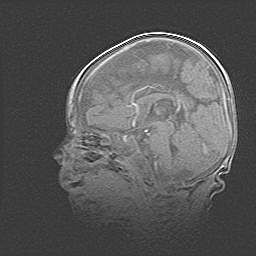

Мальформация Денди-Уокера. Киста задней черепной ямки.

Агенезия мозолистого тела.

Возраст: 2,5 месяца

Вес: 2420 г

Пол: женский

Окружность головы: 37 см

Срок гестации: 32 недели

Мальформация Денди—Уокера — редкий вид патологии ЦНС, представляющий собой врожденный порок развития каудального отдела ствола и червя мозжечка, ведущий к неполному раскрытию срединной (Мажанди) и латеральных (Лушка) апертур IV желудочка мозга. Для этогно синдрома характерна триада симптомов: гипотрофия червя мозжечка и/или полушарий мозжечка, кисты задней черепной ямки, гидроцефалия различной степени. В 70% случаев порок сочетается и с другими аномалиями головного мозга, в частности с агенезией мозолистого тела.